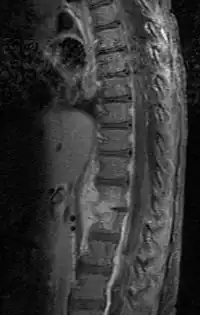

Dentro de las pruebas de laboratorio, se da un incremento del recuento de glóbulos blancos en el 13-60% de los casos. Asimismo, la tasa de sedimentación eritrocítica y los niveles de proteína C reactiva se hallan elevados en más del 90% de los casos. El gold standard para el diagnóstico de discitis es el empleo de biopsia guiada a través de tomografía axial computerizada (TAC) y la realización de un hemocultivo, dando resultado positivo en un 70-90% de los casos. Los cultivos son esenciales a la hora de determinar o descartar su posible origen bacteriano.[4]

En cuanto a las pruebas radiológicas, la radiografía arroja una sensibilidad del 82% y una especificidad del 57%. Los primeros signos radiográficos incluyen la pérdida de la lordosis lumbar, el estrechamiento del espacio intervertebral e irregularidades en la carilla articular de los cuerpos intervertebrales. La resonancia magnética nuclear tiende a arrojar resultados muy precisos, con una sensibilidad y especificidad del 95% en ambos casos.[4]